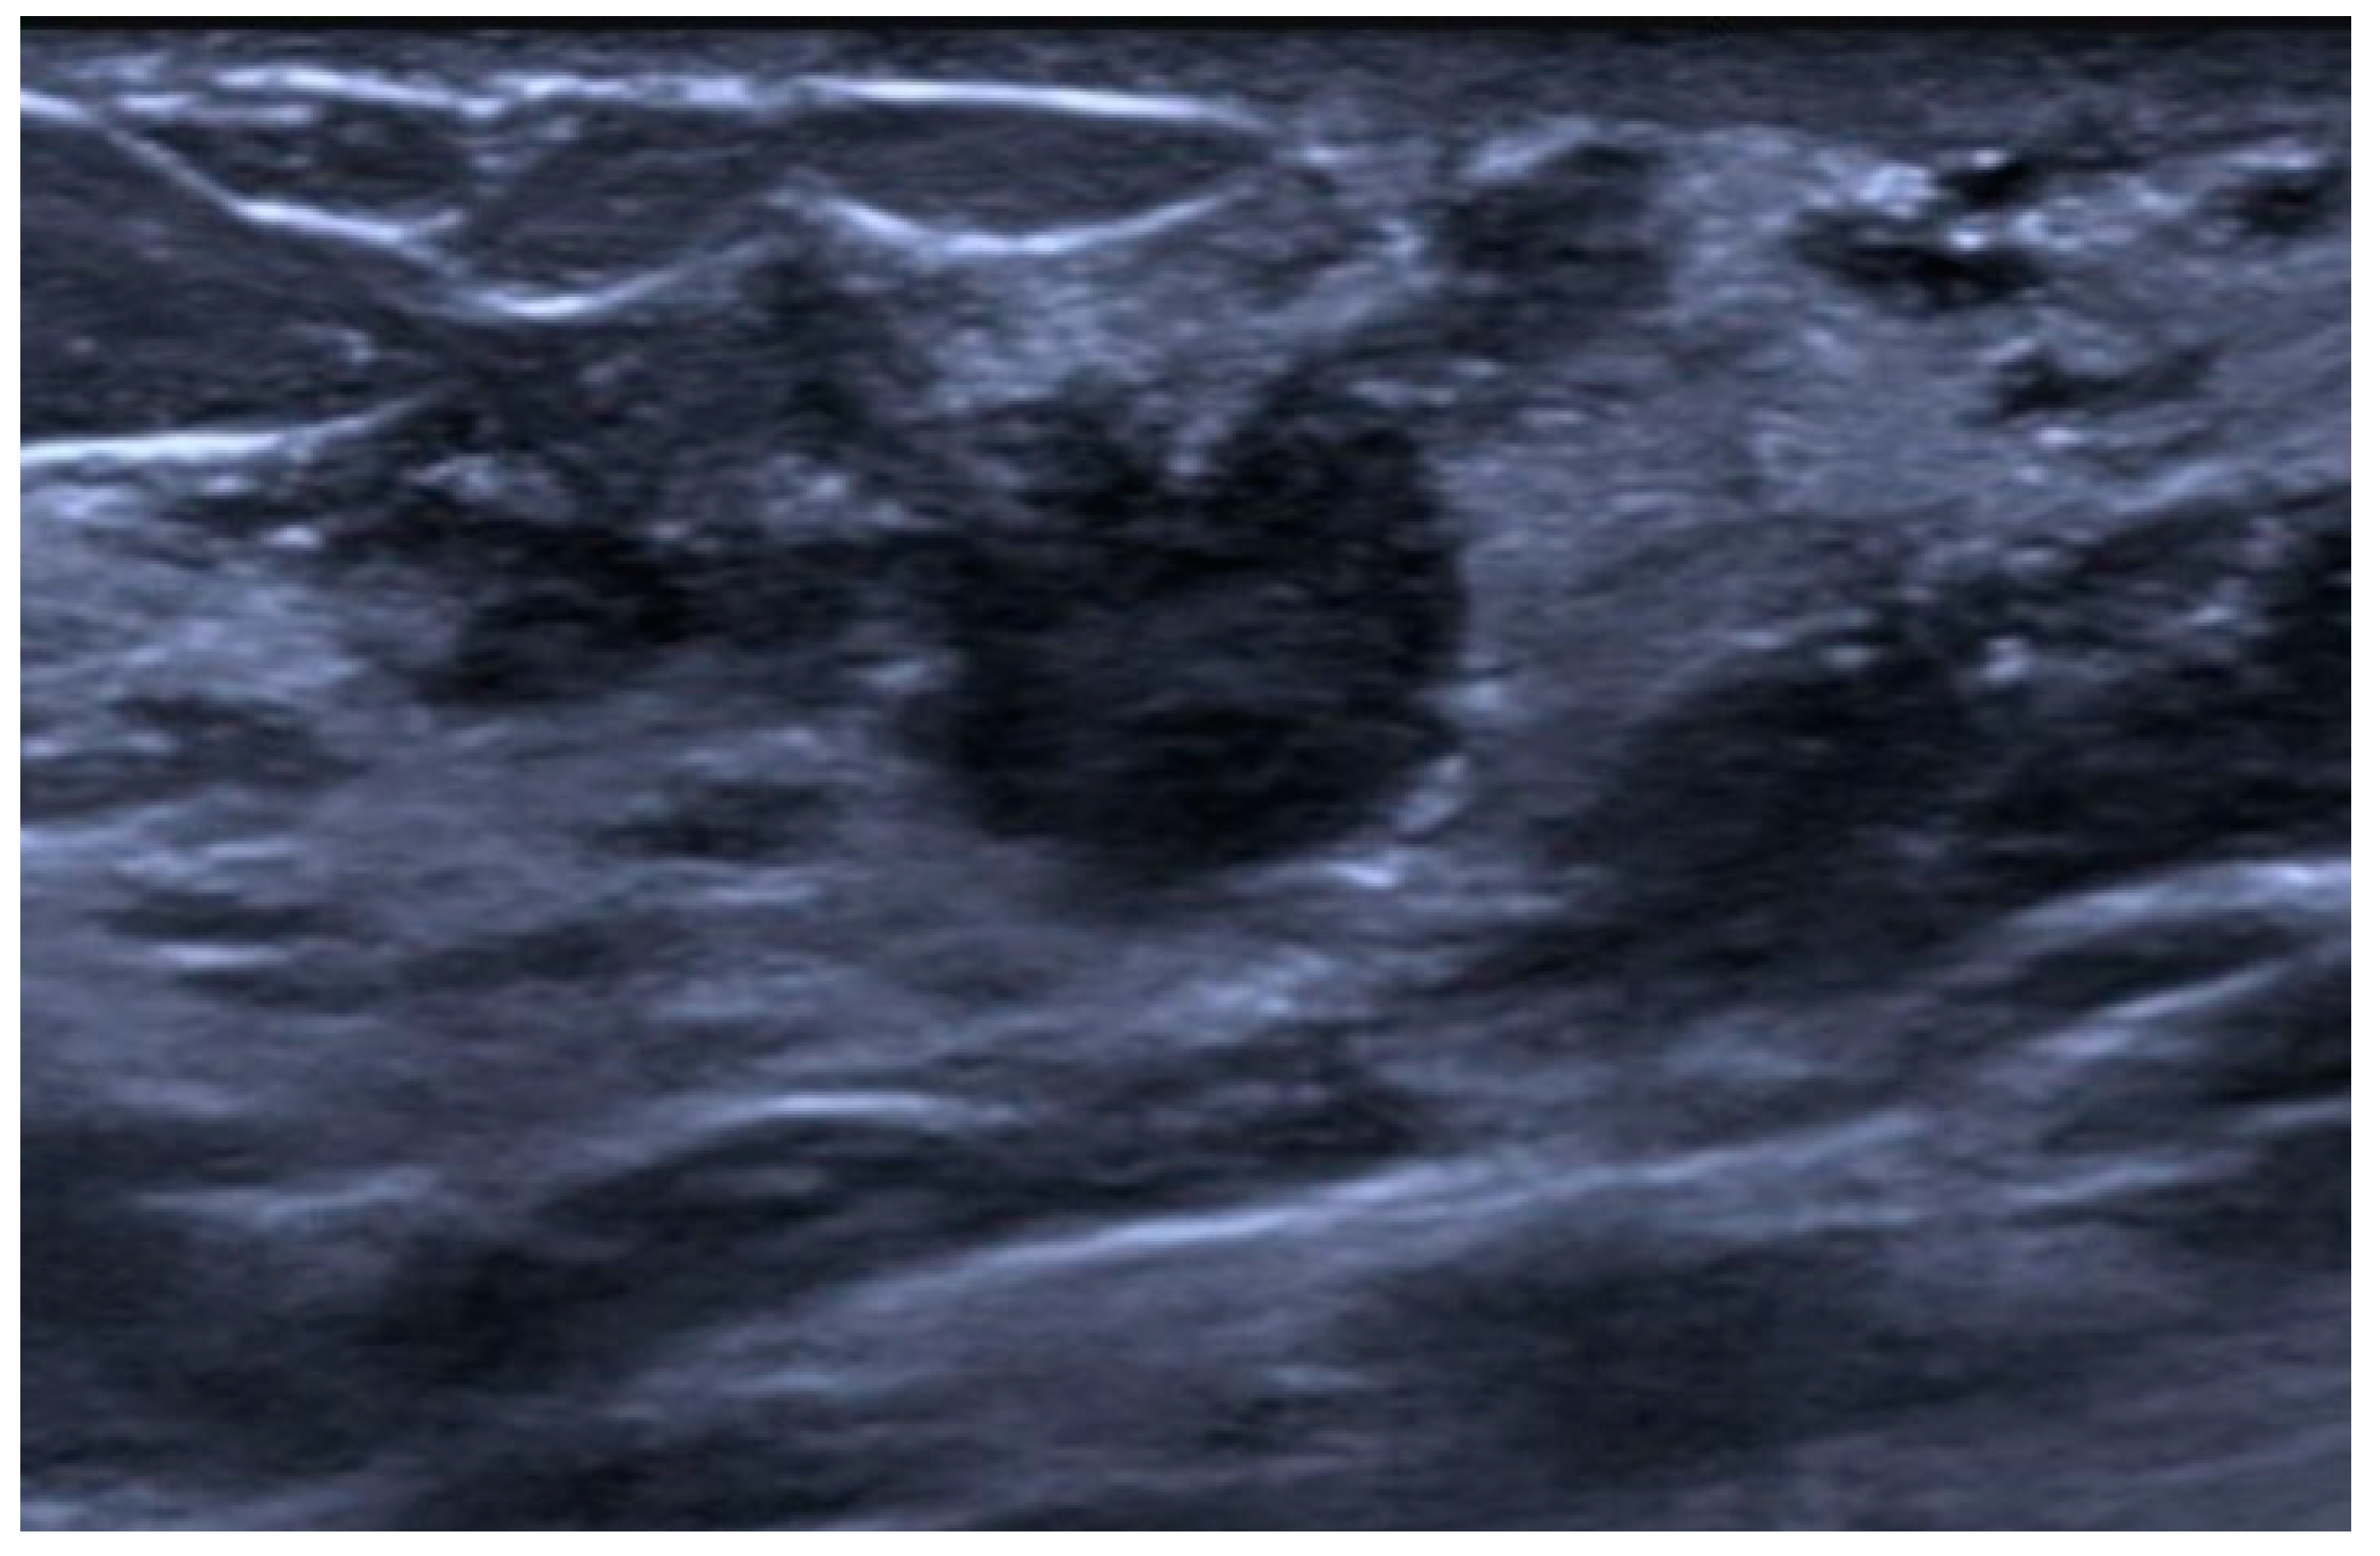

6. Medullary

- Yilmaz, E.; Lebe, B.; Balci, P.; Sal, S.; Canda, T. Comparison of Mammographic and Sonographic Findings in Typical and Atypical Medullary Carcinomas of the Breast. Clin. Radiol. 2002, 57, 640–645. [Google Scholar] [CrossRef]

- Wang, X.; Xu, P.; Wang, Y.; Grant, E.G. Contrast-Enhanced Ultrasonographic Findings of Different Histopathologic Types of Breast Cancer. Acta Radiol. 2011, 52, 248–255. [Google Scholar] [CrossRef] [PubMed]

- Tominaga, J.; Hama, H.; Kimura, N.; Takahashi, S. MR Imaging of Medullary Carcinoma of the Breast. Eur. J. Radiol. 2009, 70, 525–529. [Google Scholar] [CrossRef] [PubMed]

- Jeong, S.J.; Lim, H.S.; Lee, J.S.; Park, M.H.; Yoon, J.H.; Park, J.G.; Kang, H.K. Medullary Carcinoma of the Breast: MRI Findings. AJR Am. J. Roentgenol. 2012, 198, W482–W487. [Google Scholar] [CrossRef]